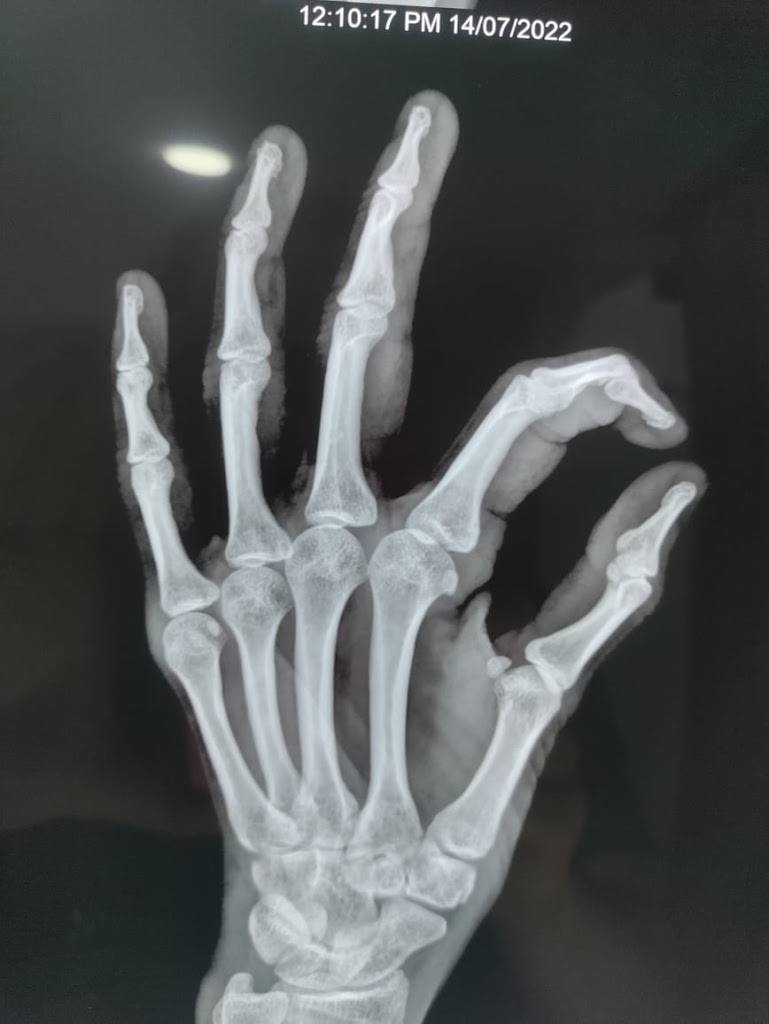

Articulaciones

La Artritis es leve y no erosiva. Aparece antes o junto con los síntomas musculares, especialmente en:

• Niños (61% presentan Artritis)

• Adultos (27.5% de prevalencia)